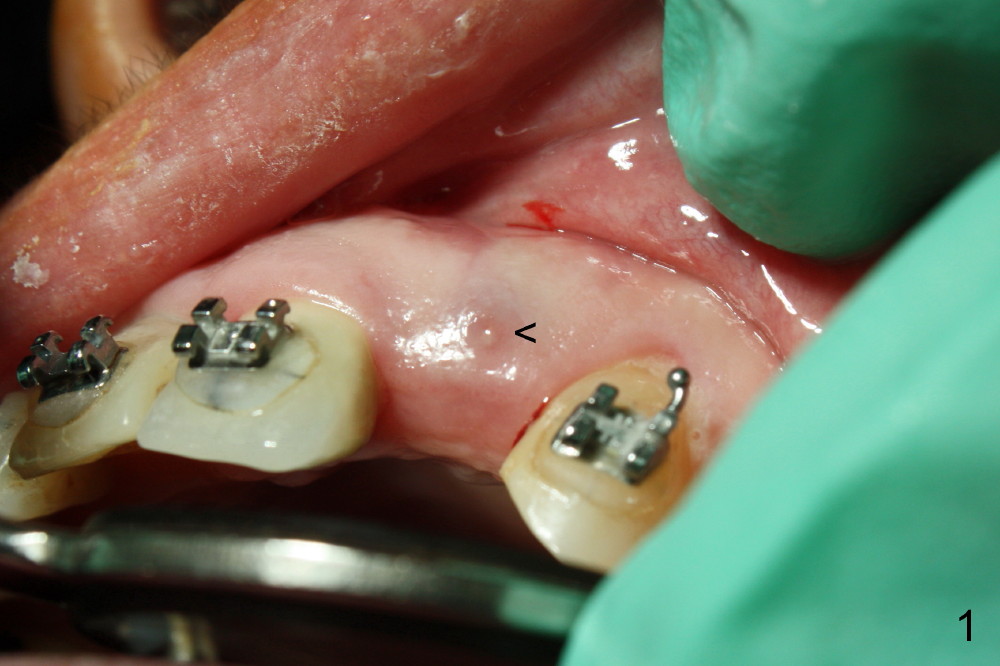

A 56-year-old Oriental lady is going to have immediate implant for the upper left lateral incisor after lengthened preparation (1 2 3 4). There is an indistinct fistula (Fig.1 <) and purulent discharge on anesthetic injection (Fig.2 <). The residual root is exposed (Fig.3 *) following a trapezoidal incision (arrowheads). After tooth extraction and socket debridement with a serrated curette (Fig.4), copious irrigation is conducted with a large monojet and normal saline (Fig.5). The socket will be soaked with non-woven gauze saturated with Clindamycin (Fig.6). The advantage of this antibiotic over Amoxicillin is that there is less mess with the former (completely dissolves). But Clindamycin is bitter. This amalgam well is saved to keep autogenous bone from the reamer and mix with allograft if needed.